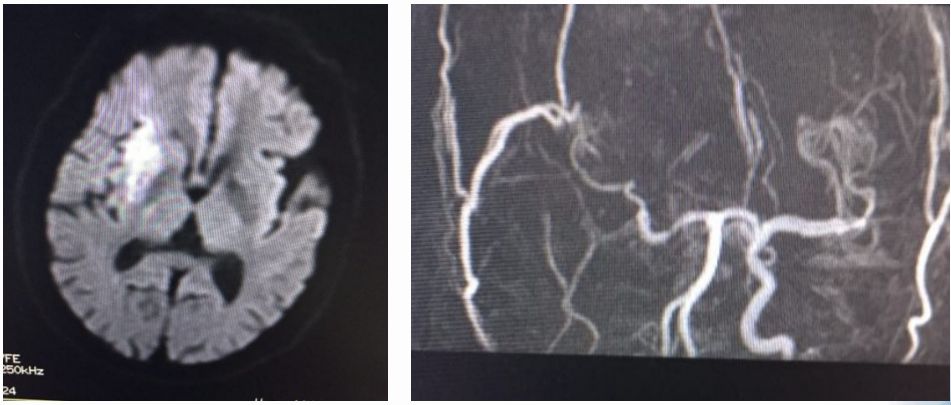

术前MR

ASPECTS评分 8分